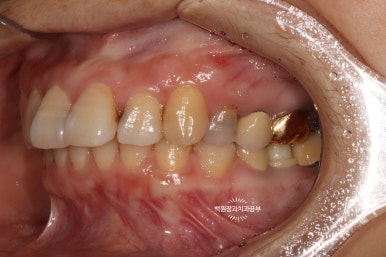

치과의사만 볼 수 있는 치아 뒷면 !!

사실 자기 앞니의 뒷면을 본 다는 것이 쉽지는 않습니다만..

치과의사는 뒷면을 볼 수 있습니다 !!!

딱 보아도 충치가 있는 걸 아실 수 있죠?

까맣게 보이는 부위들이 치아 옆면의 충치들입니다.

아까 보았던 것처럼 뒷면에서 바라본 위턱 앞니입니다.

그래서 제 생각에 앞니 레진치료를 잘 하는 사람은 당당히 치아의 뒷면을 보여줄 수 있는 치과의사라 생각해요!

보시면, 거의 색상의 차이나 경계의 구분 없이 자연스럽게 완성된 치아 외형을 관찰할 수 있습니다!